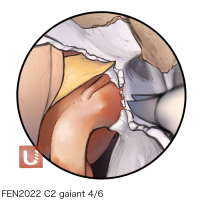

FEN2022シリーズ